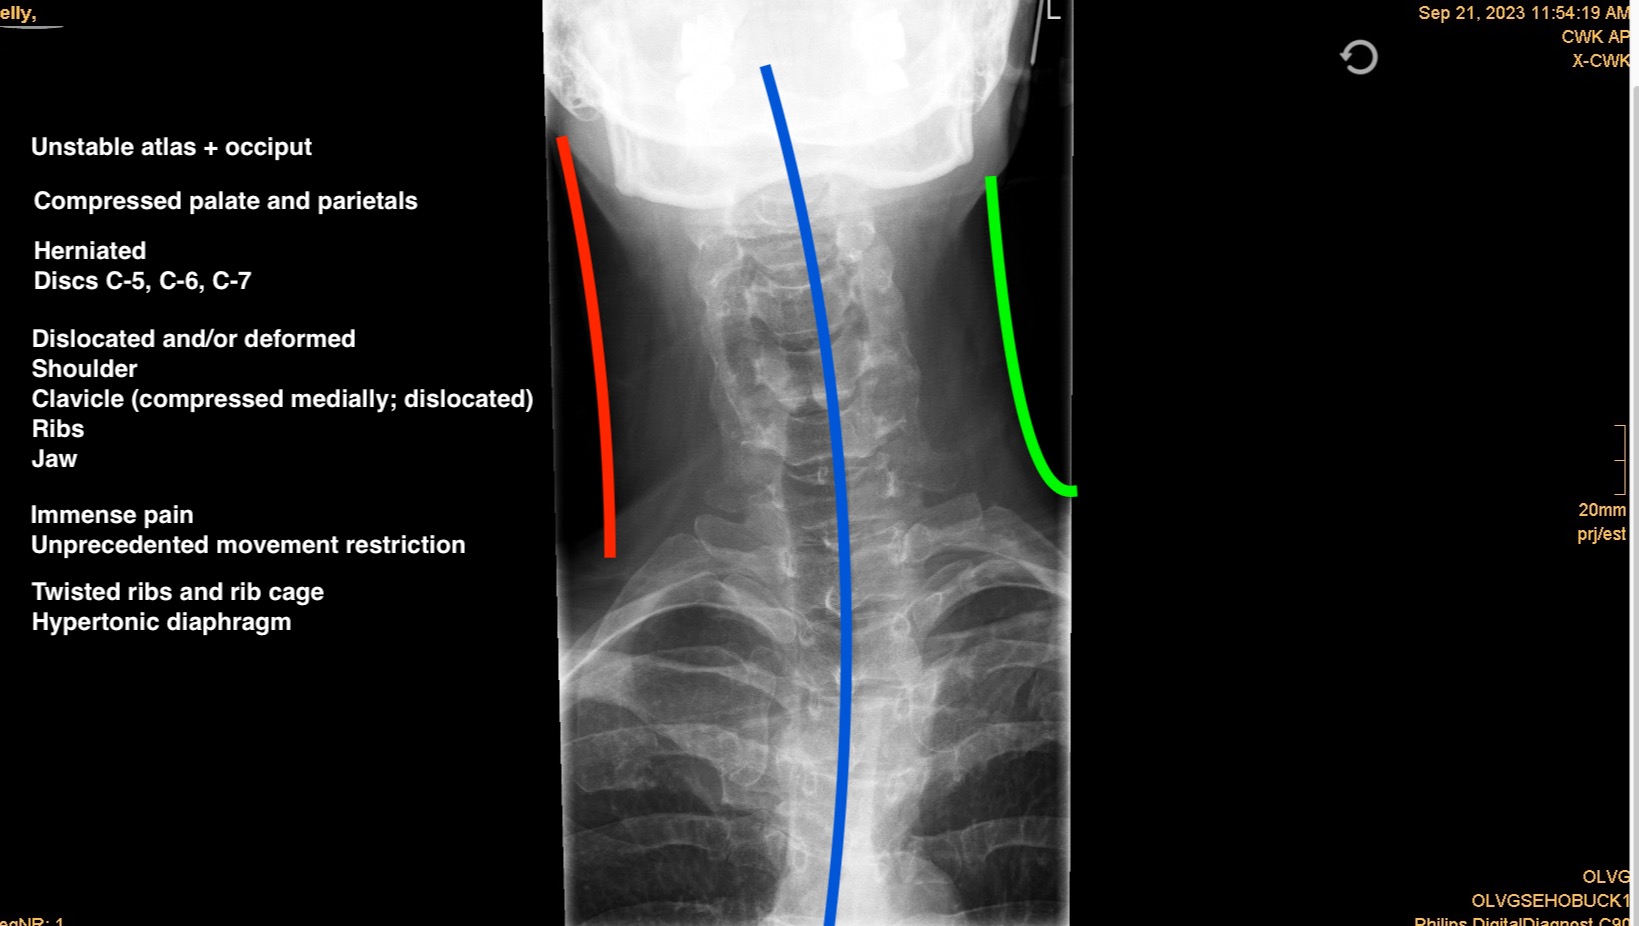

My name is Ms. Kelly. In September 2023 I was seriously injured by the hands of a bad actor (assault). I'm disfigured, disabled and in tremendous pain.

X-rays from (healthy uninjured) 2022 compared to (injured) 2023 show the significant change in alignment which alters function. The MRI reveals the injury left me with three herniated cervical discs.

I have torn ligaments, dislocated collarbone, shoulder, jaw and ribs. My spine is 'stacked', my torso compressed. The muscles in my neck, back and chest seemed to have lost most of their energy or sense of purpose. In all of this, I experience partial numbness in my lips, face, neck, hands and feet, great muscle weakness and ataxia. I feel my cervical vertebrae against my throat where it shouldn’t be.